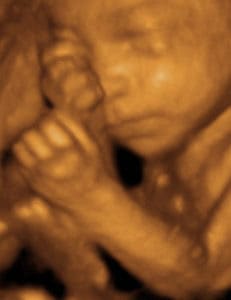

- γίνεται ο βασικότερος υπέρηχος της κύησης, αυτός του Β´επιπέδου.

Σκοπός του συγκεκριμένου υπερηχογραφήματος είναι ο πλήρης έλεγχος της ανατομίας του εμβρύου!

Ελέγχονται όλα τα όργανα του εμβρύου, η θέση του πλακούντα, το μήκος του τραχήλου της μήτρας (σημαντική μέτρηση για την πρόληψη πρόωρου τοκετού) και το φύλο του παιδιού -εάν επιθυμούν οι γονείς-.

Η συγκεκριμένη εξέταση γίνεται από εξειδικευμένο εμβρυομητρικό ιατρό.